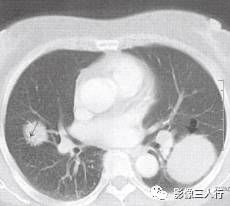

胸部CT图像显示,在含气少的致密肺的背景上见到含气的支气管,表现为两种形态: ①在大片肺实变病灶内的细条状空气密度影;②直径Imm的小泡状空气密度影,连续的几 个层面都能出现(图2、图3)。该征象表明:①近侧气道通畅;②肺泡内的空气经吸收(肺不张)或取代(肺炎、肺癌),或两者综合而消失。通畅含气的支气管在肺泡实变高 密度区内表现为管腔内低密度充气轮廓。 医学百科网 | YxBaike.Com